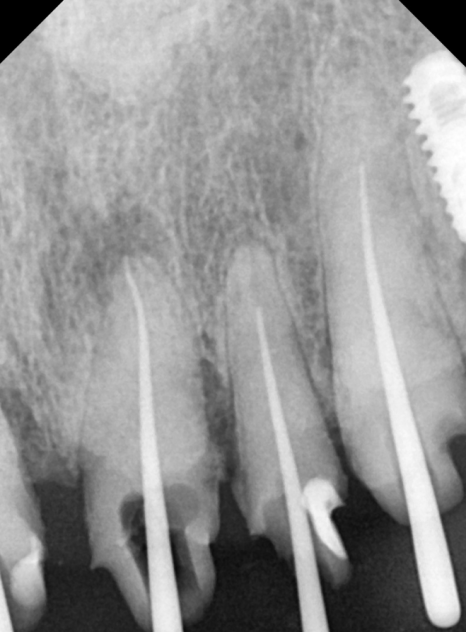

방사선 사진을 살펴보니,

충치가 신경까지 아주 가깝게

진행되어 있었는데요...

240223